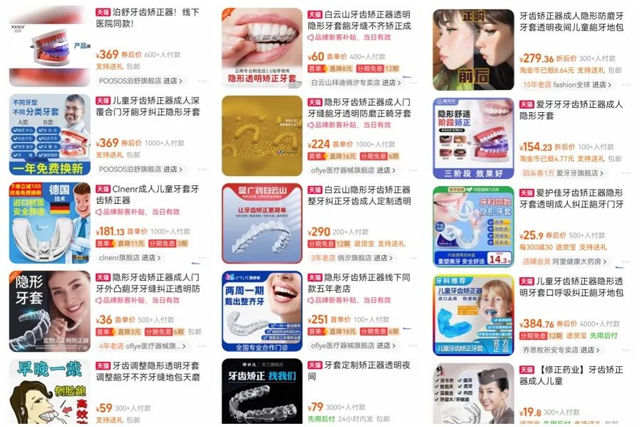

如今越来越多的人开始注重牙齿的美观:“不用跑医院,低价就能变美!”——铺天盖地的广告让隐形牙套成了电商平台的“爆款”。但撕开“便捷”“高科技”的包装,背后藏着的却是触目惊心的风险……

而网购的隐形牙套基本为均码设计,且所谓“量身定制”的隐形矫正服务,实则是为消费者远程寄送牙模材料自行取材,全程缺乏专业医生面诊评估咬合关系、牙槽骨条件及牙周健康状况,可能忽略颌骨畸形、牙根短/吸收等问题,盲目施力轻则造成牙齿疼痛,重则可能导致牙周炎、牙根吸收甚至脱落、骨开窗、骨开裂等比较严重的牙周问题。

问:电商平台部分商家宣称“数字化定制牙套”、“线上复诊方便”,这类说法是否可靠?普通消费者要如何辨别合规的正畸产品与服务?

袁曦:我们需要在正规的医院进行常规检查,通过专业医生的分析给出具体的个性化方案,而不是说自行通过网上搜索就能进行牙齿矫正,这样是非常不可取的。如果连常规检查都没做就直接佩戴牙套,肯定是不合规的。